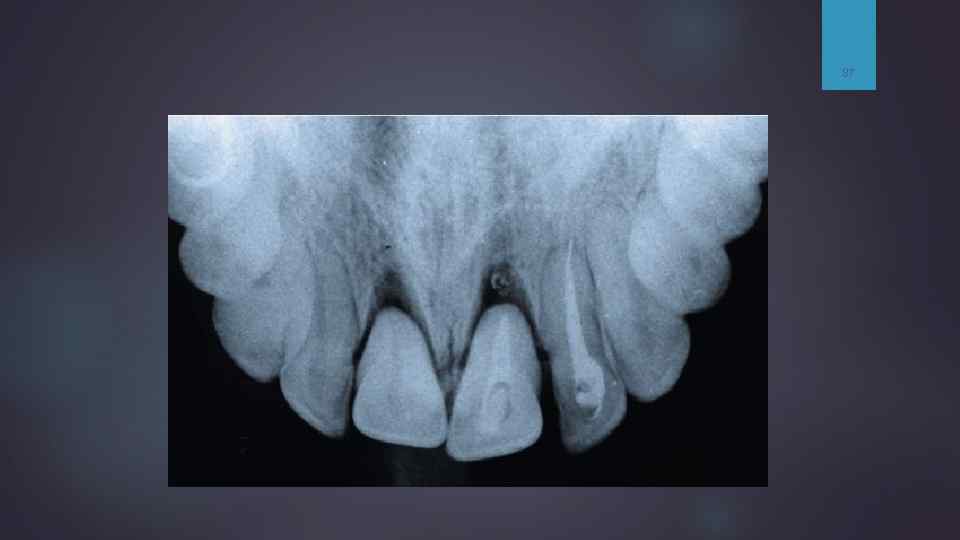

Методы лучевой диагностики Рентгенография: контактная окключионная (в прикус) 86

87

Рентгенограмма переднего отдела нижней челюсти вприкус. Открытый перелом альвеолярной части в области 2. 1 -1. 2 со смещением отломка.

Внутриротовая рентгенограмма переднего отдела верхней челюсти вприкус. Поперечный перелом корня 21 зубы шинированы.